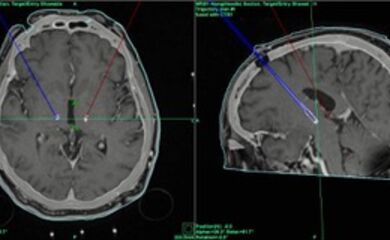

Die Elektroden für die Tiefe Hirnstimulation werden in einem sog. stereotaktischen Eingriff eingesetzt. Hierbei handelt es sich um ein minimalinvasives Operationsverfahren, bei dem Ihr Kopf in einem Stereotaxierahmen, eine Art Ring um den Kopf, fixiert wird. So wird ein Verwackeln verhindert und die Elektroden können computergestützt wie in der vorangegangenen MR-Planungsbildgebung geplant millimetergenau platziert werden. Noch im Operationssaal wird computertomographisch anschließend die korrekte Lage der Elektroden überprüft.

Für die Operation der Tiefen Hirnstimulation wird die sogenannte rahmenbasierte Stereotaxie als hochpräzises, bildunterstütztes Verfahren angewandt.

Hierbei wird ein Stereotaxierahmen zur OP am Kopf angebracht und eine spezielle CT-Bildgebung durchgeführt, die es erlaubt im Abgleich mit dem präoperativen Planungs-MRT den sicheren Weg von der Hirnoberfläche bis in die gewünschte Zielregion in Einstellungen für das millimetergenaue Setzen der Elektroden zu übersetzen.

Eine intraoperative Kontroll-Computertomografie belegt die korrekte Lage der Elektroden auch im Abgleich zum präoperativen Plan, bevor anschließend der Schrittmacher im Bereich des Brustkorbs unter dem Schlüsselbein, sowie Verlängerungskabel zwischen Hirnelektroden und Schrittmacher implantiert.